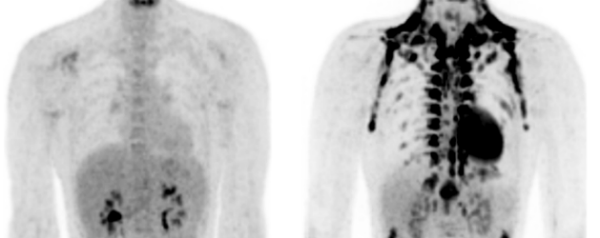

“Bruin vet neemt vetten op vanuit het bloed, maar in plaats van die op te slaan, verbrandt het ze voor de productie van warmte. Het bruin vet is dus een soort kacheltje dat je warmt houdt”, legt Nahon uit. “Van dit bruin vet was al bekend dat het in grote hoeveelheden in baby’s voorkomt, die dit nodig hebben om hun lichaamstemperatuur op peil te houden. Dat ook volwassenen bruin vet hebben, kwam als een verrassing.”

Verder is ontdekt dat slanke mensen meer van dit vetverbrandende bruin vet hebben dan mensen met overgewicht, zegt Nahon. “Dit maakt bruin vet nog interessanter! Door het bruin vet te activeren zou je dus letterlijk de extra kilo’s vet weg kunnen smelten. Daarom wordt er nu veel onderzoek gedaan naar manieren om het bruin vet harder te laten werken of te vermeerderen.”